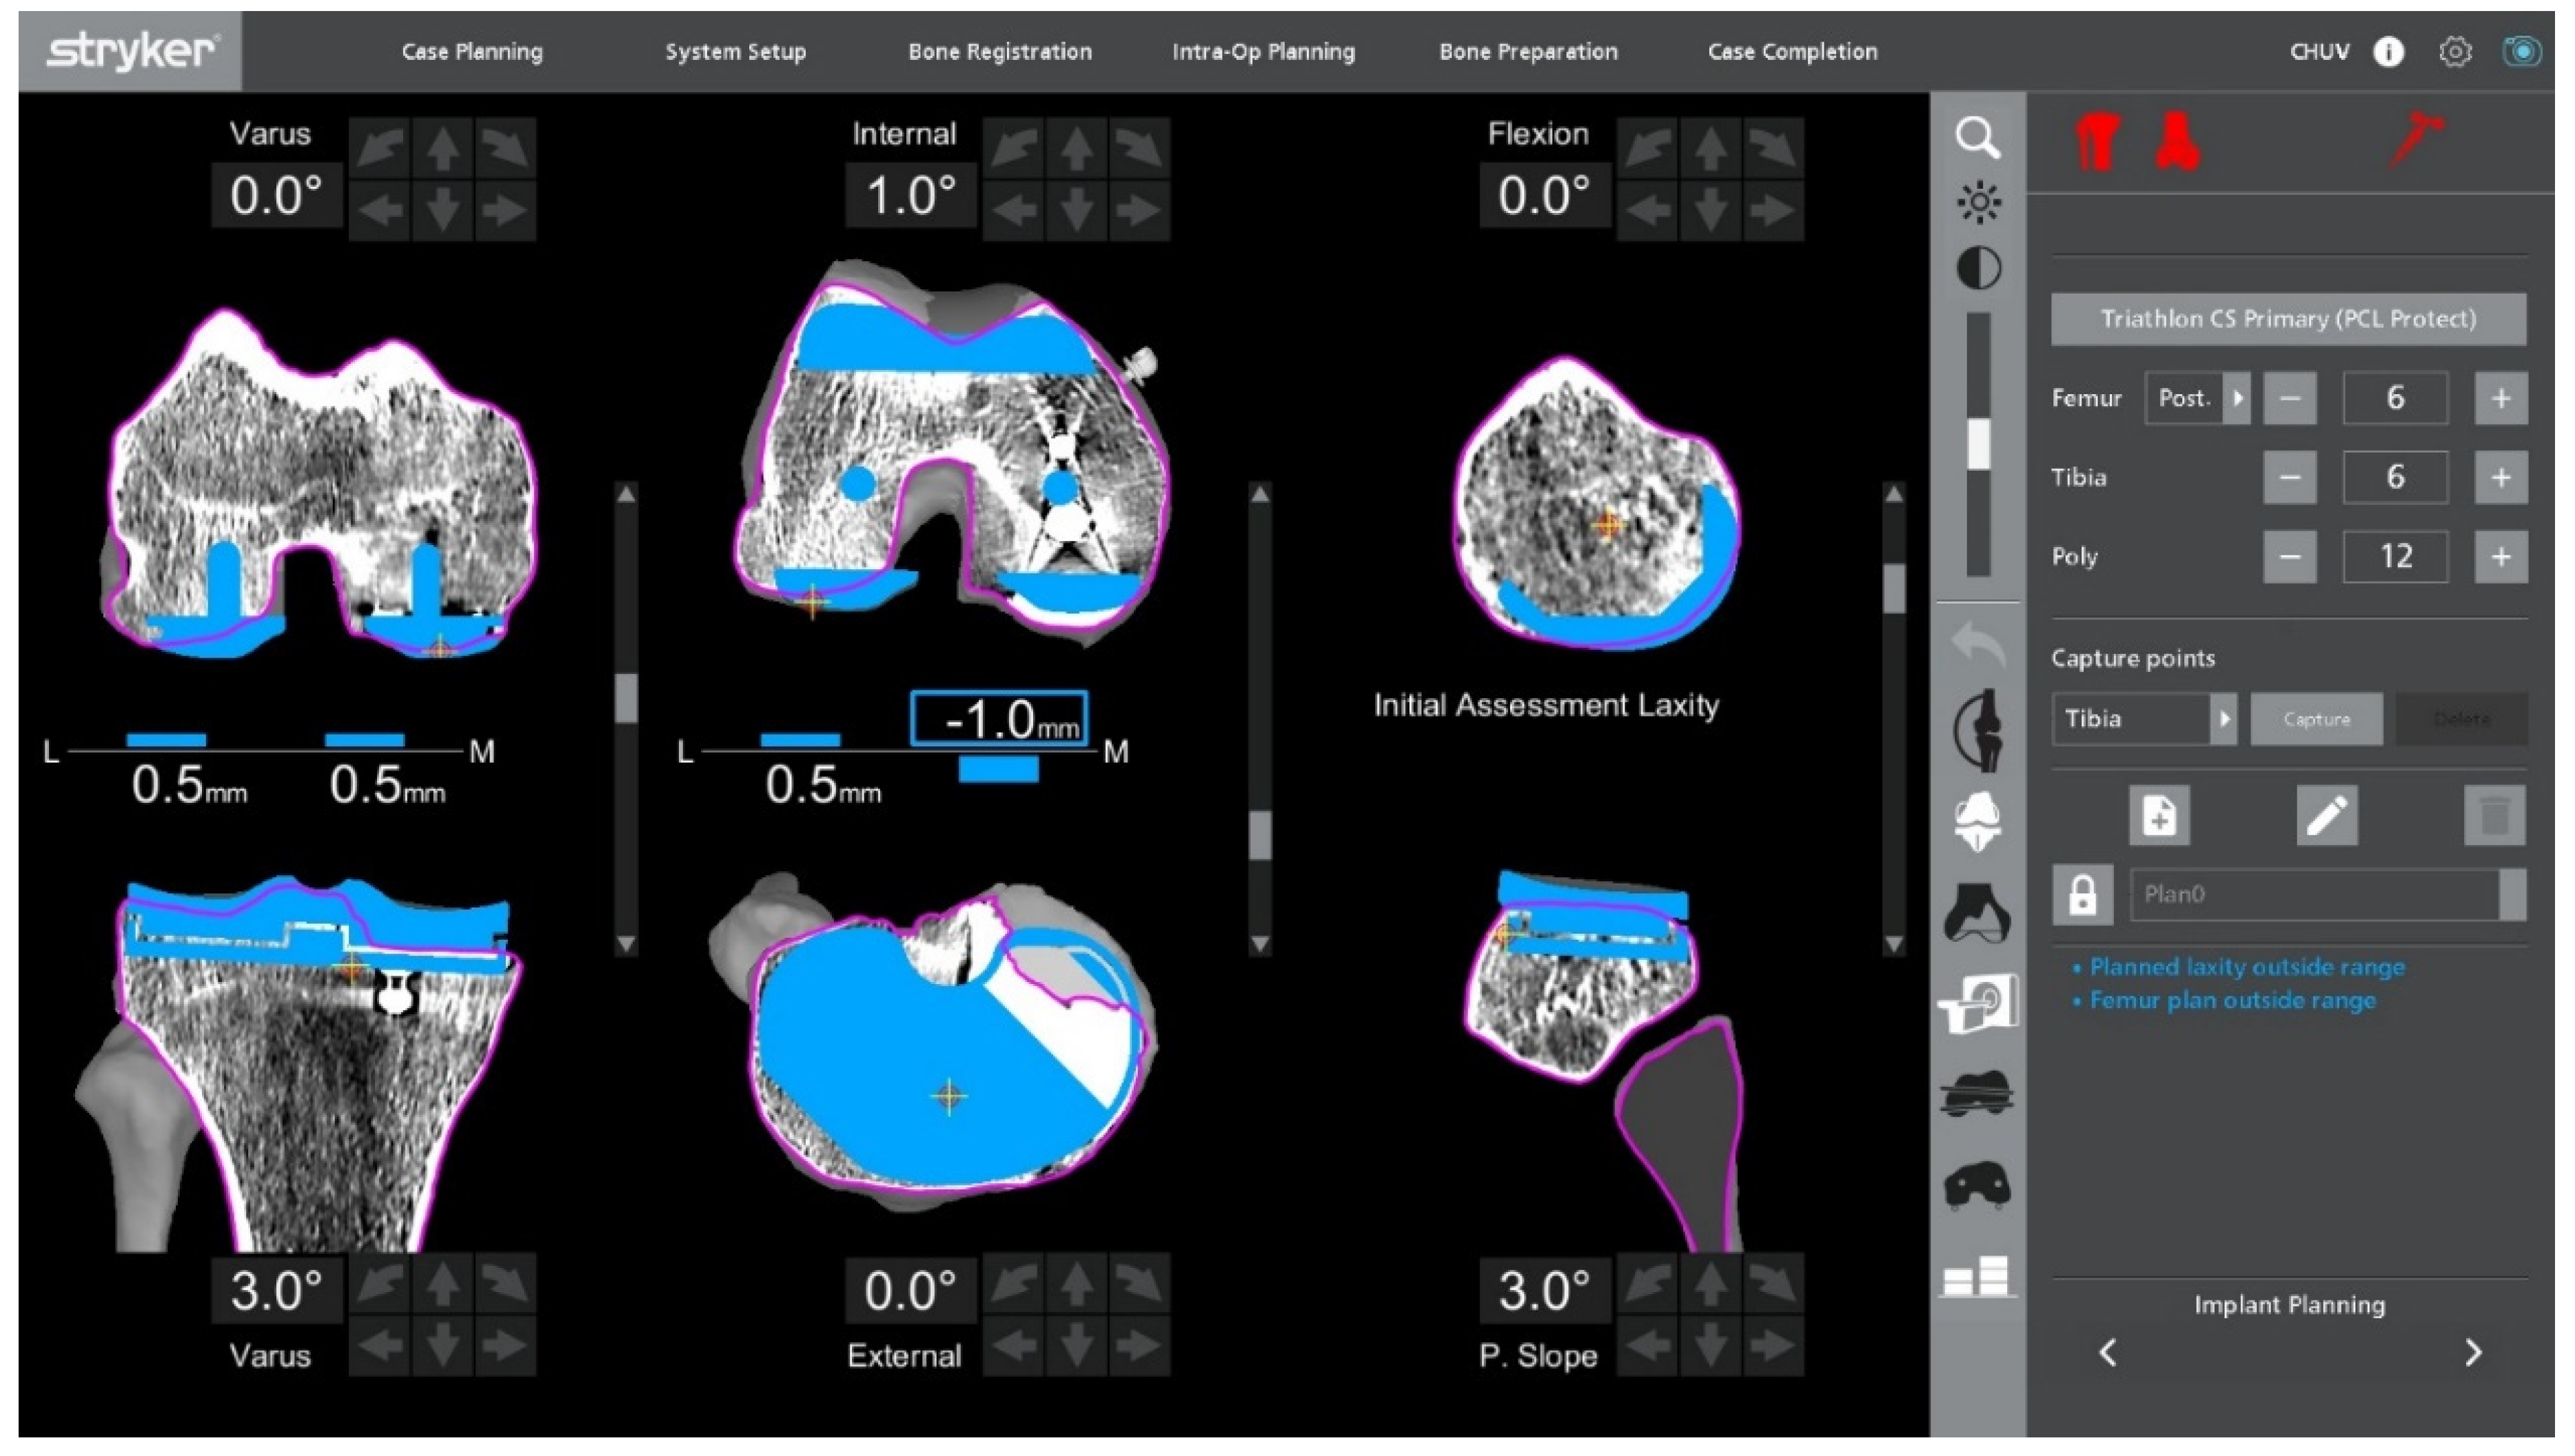

2.6. Robotic Planning and Bone Resection

After confirming ligament balance, the preoperative plan is adjusted if necessary to optimize bone preservation and soft-tissue tension. Robotic-guided resections are performed according to the final plan (Figure 5). The intraoperative screen may display a plan with submillimetric residual gaps, which is an intended target and acceptable without stress testing at this stage. At 90° of flexion, a small sub-millimetric lateral laxity is acceptable and often desirable to permit a physiological medial-pivot pattern while maintaining coronal stability.

Figure 5.

Final adjusted implant positioning and robotic resection plan after gap assessment, intentionally showing sub-millimetric residual gaps at the no-stress stage. Planning aims optimize ligament balance while preserving bone.